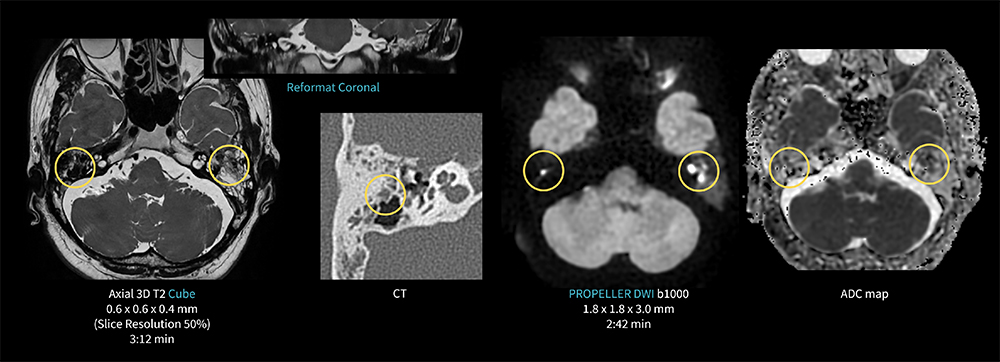

Case3 Cube & PROPELLER DWI/真珠腫

40代、男性。左耳閉感にて左中耳真珠腫疑いのため聴神経MRI検査を施行した。

Thin sliceやReformatでの観察のため、AIR Recon DLを併用した3D Cubeを撮像し、磁化率アーチファクトを抑えるため、DWIはAIR Recon DLを併用したPROPELER DWIを撮像。

空気による歪みを抑え、左鼓室から乳突洞に真珠腫、さらには右乳突蜂巣内の真珠腫が明瞭に高信号として確認された。

MR30_Kariyatoyota_05.jpg図3 CubeとPROPELLER DWIを用いた真珠腫の描出